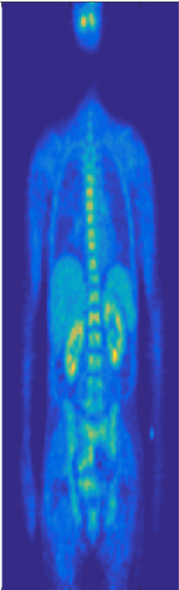

For evaluation, we use three different datasets: a) 58 whole body PET scans of resolution . We randomly pick 10 whole body volumes for testing and train with the 48 remaining volumes. We normalize the intensity range of our training and testing volumes using the min-max method based on min and max intensity values of the whole training set. Next, in both training and testing, each single sub-volume is also normalized to using its min and max before feeding it into network. b) 958 MRI prostate scans of different resolution which were resampled to voxel size of . We randomly picked 258 volumes for testing, and train with remaining 700 volumes. c) hlUltrasound echocardiography images of resolution , used for left ventricular myocardial segmentation, were split into 430 train and 20 test. The datasets were collected internally and from The Cancer Imaging Archive (TCIA) QIN-HEADNECK and ProstateX datasets [26, 27, 28, 29, 30]. Samples of the three datasets are shown in Fig. 2.

a) PET multi-organ segmentation: For training the PET multi-organ segmentation network, from each training image, we extract 100 randomly positioned -voxel sub-volumes per organ (5 organs in total: brain, heart, left kidney, right kidney, and bladder) and another 100 for negative background sub-volumes. Therefore, we train all the models with number of training volumes. In test, the striding size was set to . PET volumes size varied from to . We train and test all the models using two Titan-X GPUs in parallel each with batch-size 1.